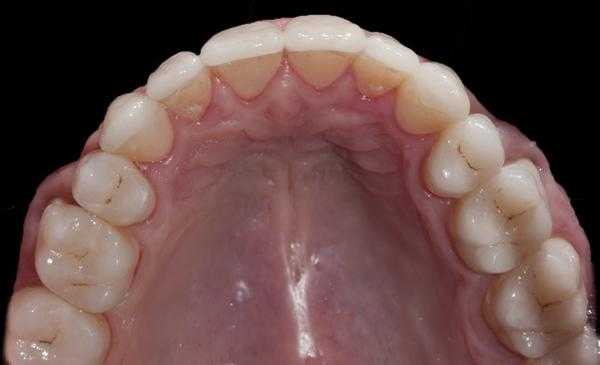

После этого в лаборатории были изготовлены vonlays (фото 10-14). Для этого авторы статьи обычно используют e.max в области моляров, ведь успехи подобного подхода уже хорошо задокументированы, но иногда можно использовать и полевошпатную керамику, особенно в случаях с достаточным количеством эмали, или когда премоляры лечат параллельно с установкой виниров на фронтальных зубах. Авторы по-прежнему предпочитают использовать протокол тотального протравливания с бондом 4-го поколения, хотя перспективы «универсальных» адгезивов и результаты, полученные в ходе их исследований, тоже не могут не радовать. На фото 15-29 продемонстрировано восстановление дуги верхней челюсти с использованием виниров во фронтальной области и керамических vonlays-конструкций на жевательной группе зубов.

Фото 15-21. Последовательность клинических процедур: вид до вмешательства, вид прототипа, удаление прототипа, дефектных амальгамных пломб и остальных реставраций, нанесение кариес-маркера, запечатывание дентина и заполнение поднутрений, установка окончательных реставраций.

Фото 26. Вид после вмешательства.